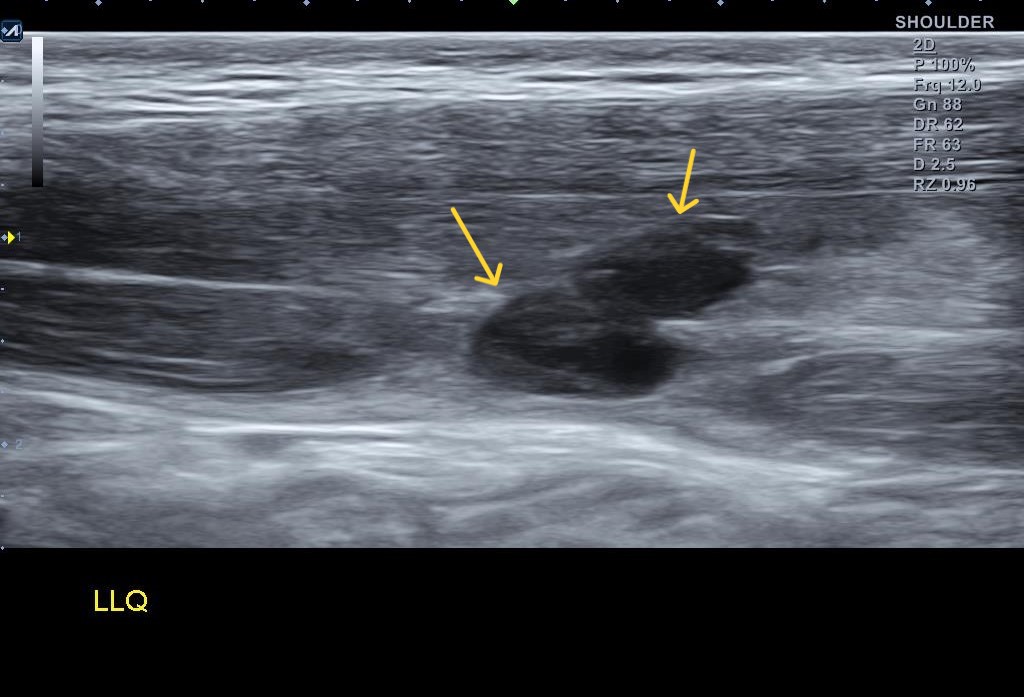

당산정형외과 당산역정형외과 당산동정형외과 여의도정형외과 합정정형외과 목동정형외과 영등포정형외과 영등포구청정형외과 선유도정형외과 도수치료 박상준의원)안녕하세요 박상준원장입니다. 오늘은 얼마전에 어깨 통증으로 방문한 환자 이야기를 해볼까 합니다. 나 : 어디가 불편해서 오셨어요?환자 : 어깨가 아픕니다.나 : 아픈지 얼마나 되셨나요?환자 : 그게.... 대략 3년정도 되었네요 꽤 오랜시간 어깨가 아팠다는 환자분.... 나 : 아프신지가 꽤 오래되었네요? 병원은 처음 오신 거에요?환자 : 네 아프지는 오래되었는데 ... 병원은 처음이네요... 제가 아픈걸 잘 참아서요... 아픈걸 잘 참아왔다는 환자분..... 그런데 나 : 병원 방문을 결심하신 이유가 있나요?환자 : 그동안은 그럭저럭 지냈는데.... 몇주전..